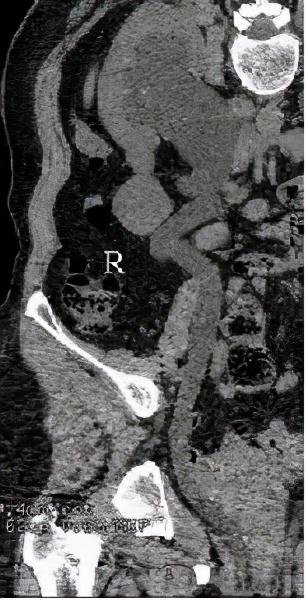

检查完成后,CT也印证了双肾积水的表现。

但是,双侧输尿管走行区未见明显梗阻的因素。

同时也发现了异常表现:双侧输尿管开口过低,似乎不是正常的膀胱三角区。

在增强CT检查的时候,得到了如下检查图像

检查图像显示,该病人的双侧输尿管于膀胱开口处过低,还伴有左侧部分双肾盂、输尿管畸形,这些图像给我们的印象是:是不是存在异位开口的可能?